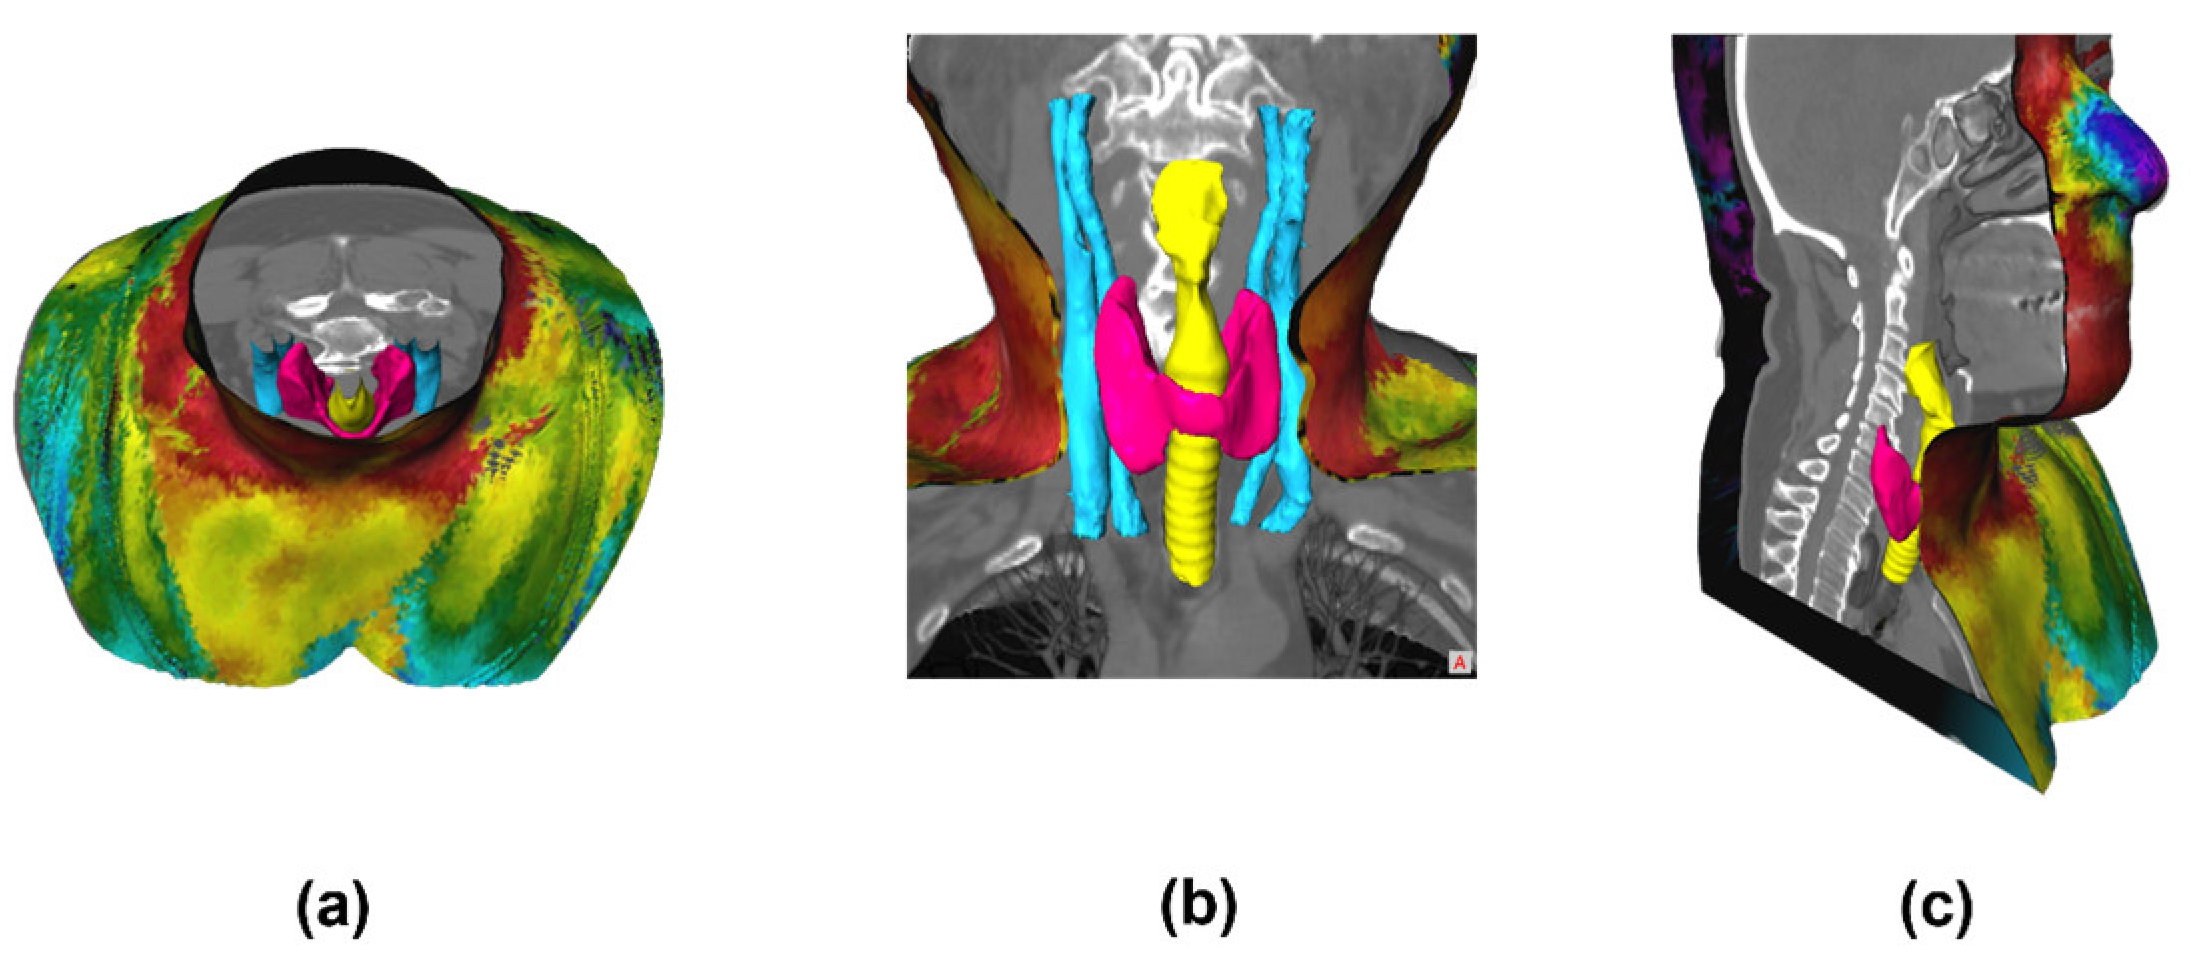

4.3. Generation of 3D THERMO-SCAN Model: Complete 3D Visualization

The final visualization of the complete 3D model obtained using the MeVisLab® software demonstrates the fusion and registration between the 3D thermal shell and the DICOM data (i.e., the CT anatomical images), presented in Figure 19.

Figure 19.

The results were visualized after the fusion between the 3D thermal shell (external) with the DICOM data (internal).

On the inside of the complete 3D model, a set of segmented structures are presented where it is possible to observe the following structures: thyroid (pink), trachea (yellow), and veins and arteries (blue) (as seen in Figure 20). Also, a video overview illustrating these results can be found in the Supplementary Information (Video S1). These inner colors were chosen to highlight and emphasize the anatomical region under analysis. These views are obtained through the View3D module, to control the cuts through the SoClipPlane module in the MeVisLab® software.

Figure 20.

3D visualization of the complete model, showing the structures in different sections/slices: (a) axial, (b) coronal, and (c) sagittal. A video overview illustrating these results can be found in the Supplementary Material (Video S1).